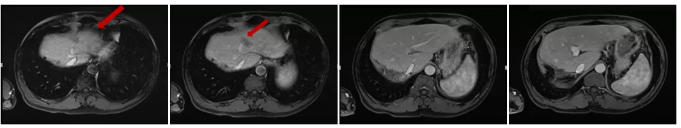

MRI检查结果:肝脏多发异常信号影,多为转移瘤。

肝脏MRI检查

2017.12复查 MRI示:肝左外叶见一斑片状稍长T1稍长T2信号影,横截面约1.4cm×1.4cm,增强扫描边缘强化。